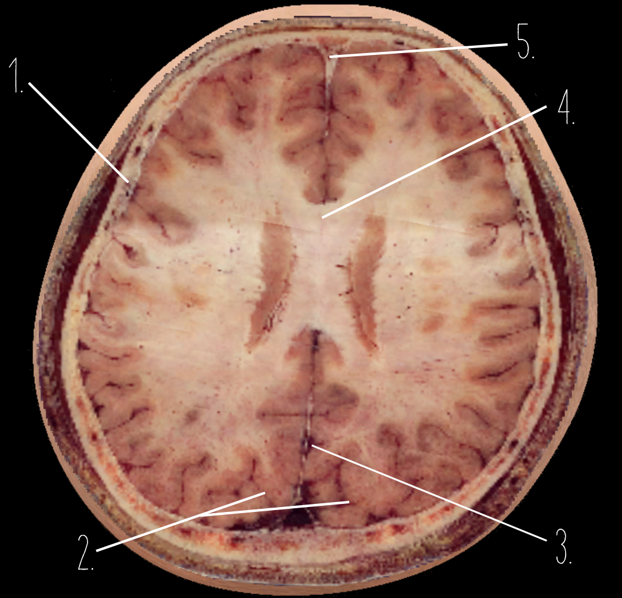

1?

Choroid Plexus

2?

Lateral Ventricle

3?

Caudate Nucleus

4?

Third Ventricle

5?

Parietal Bone

6?

Occipital Bone

7?

Falx Cerebri